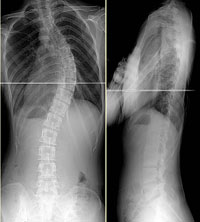

척추측만증 사진

| 경증측만증 |

중증측만증 |